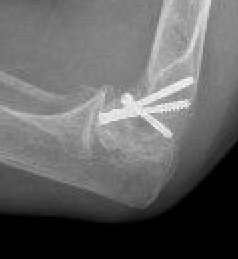

Fixation

Headless compression screws AP / PA

Posterolateral plate

Lateral approach and ORIF

Usually AP headless compression screws (violates articular surface)

- +/- PA screws (risk AVN)

- +/- excise isolated cartilage lesions

- +/- postero-lateral plate

ORIF with PA screws and posterolateral plate

Large capitellum fracture / lateral column ORIF with plate and screws